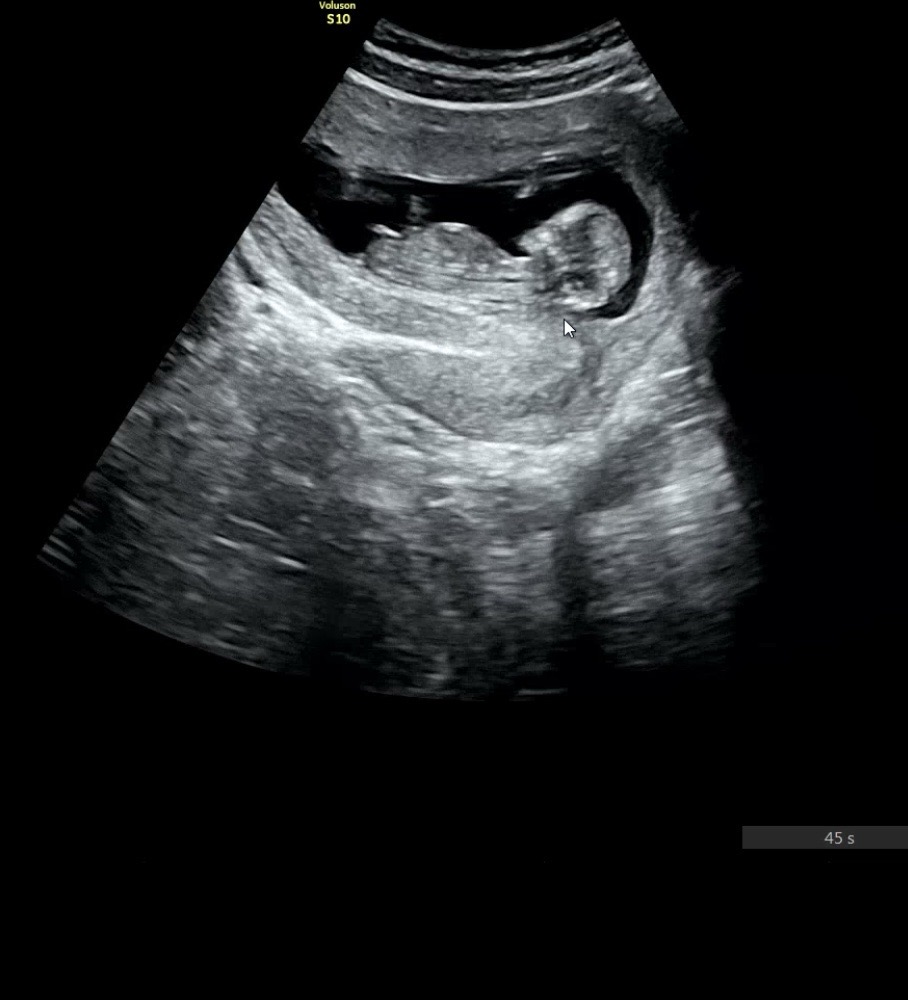

12주 0일 각도법 한 번만 봐주세용🥹

잘 안보이는 것 같긴 한데 아들일지 딸일지 한 번만 봐주세요🙏🏻 그리고 다들 즐거운 추석 보내세요〰🍁